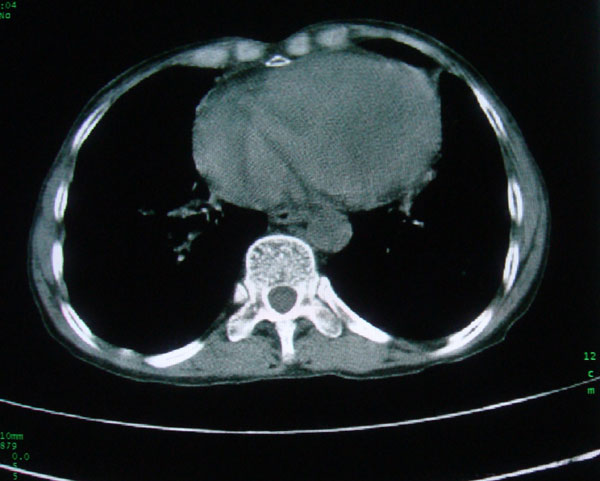

标题: CT15046:F59Y,咳嗽间断咳血丝痰就诊. [打印本页]

咳嗽\间断咳血丝痰就诊.

本例应该是“慢性疾病并发多种合并症”即:慢支并感染并支气管扩张征!结合病灶分布 形态分析,不除外合并“继发性肺结核”!

慢性支气管炎伴支气管扩张\\感染

肺间质性改变 支气管扩张合并感染

慢性支气管炎伴全小型肺气肿、支气管扩张、感染、间质纤维化。